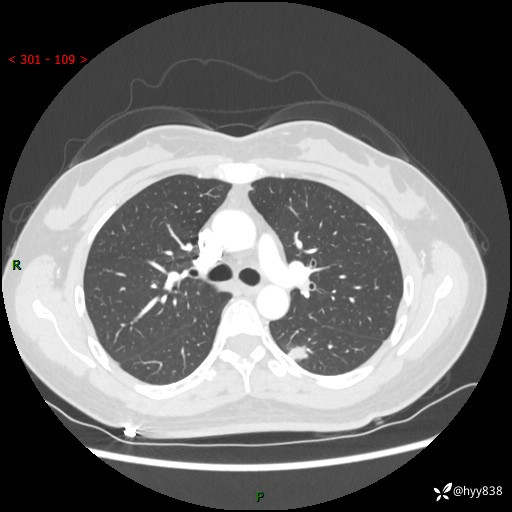

【患者信息】:36岁/女

【主诉】:左侧下胸部阵发性疼痛2周,乏力1周

【现病史及既往史】:患者自诉2周前饮酒后出现左侧下胸部阵发性疼痛,不随呼吸改变,无咳嗽咳痰、头晕头痛、咳血、呼吸困难等不适,于当地第一人民医院查胸部CT提示肺部感染,随后前往我院门诊给予抗感染(左氧氟沙星)治疗1周,自诉胸痛较前好转,感乏力、头晕,偶尔干咳,无咳痰,无发热、畏寒、胸闷、咯血、四肢酸痛、腹泻、腹痛等不适,门诊复查胸部CT提示:左肺下叶感染,病灶较前增加增大,遂以“肺部感染”收入我科。 起病以来,患者精神、饮食、睡眠可,大小便正常,体力体重无明显变化。

【检查】:胸部CT增强(外院平扫)